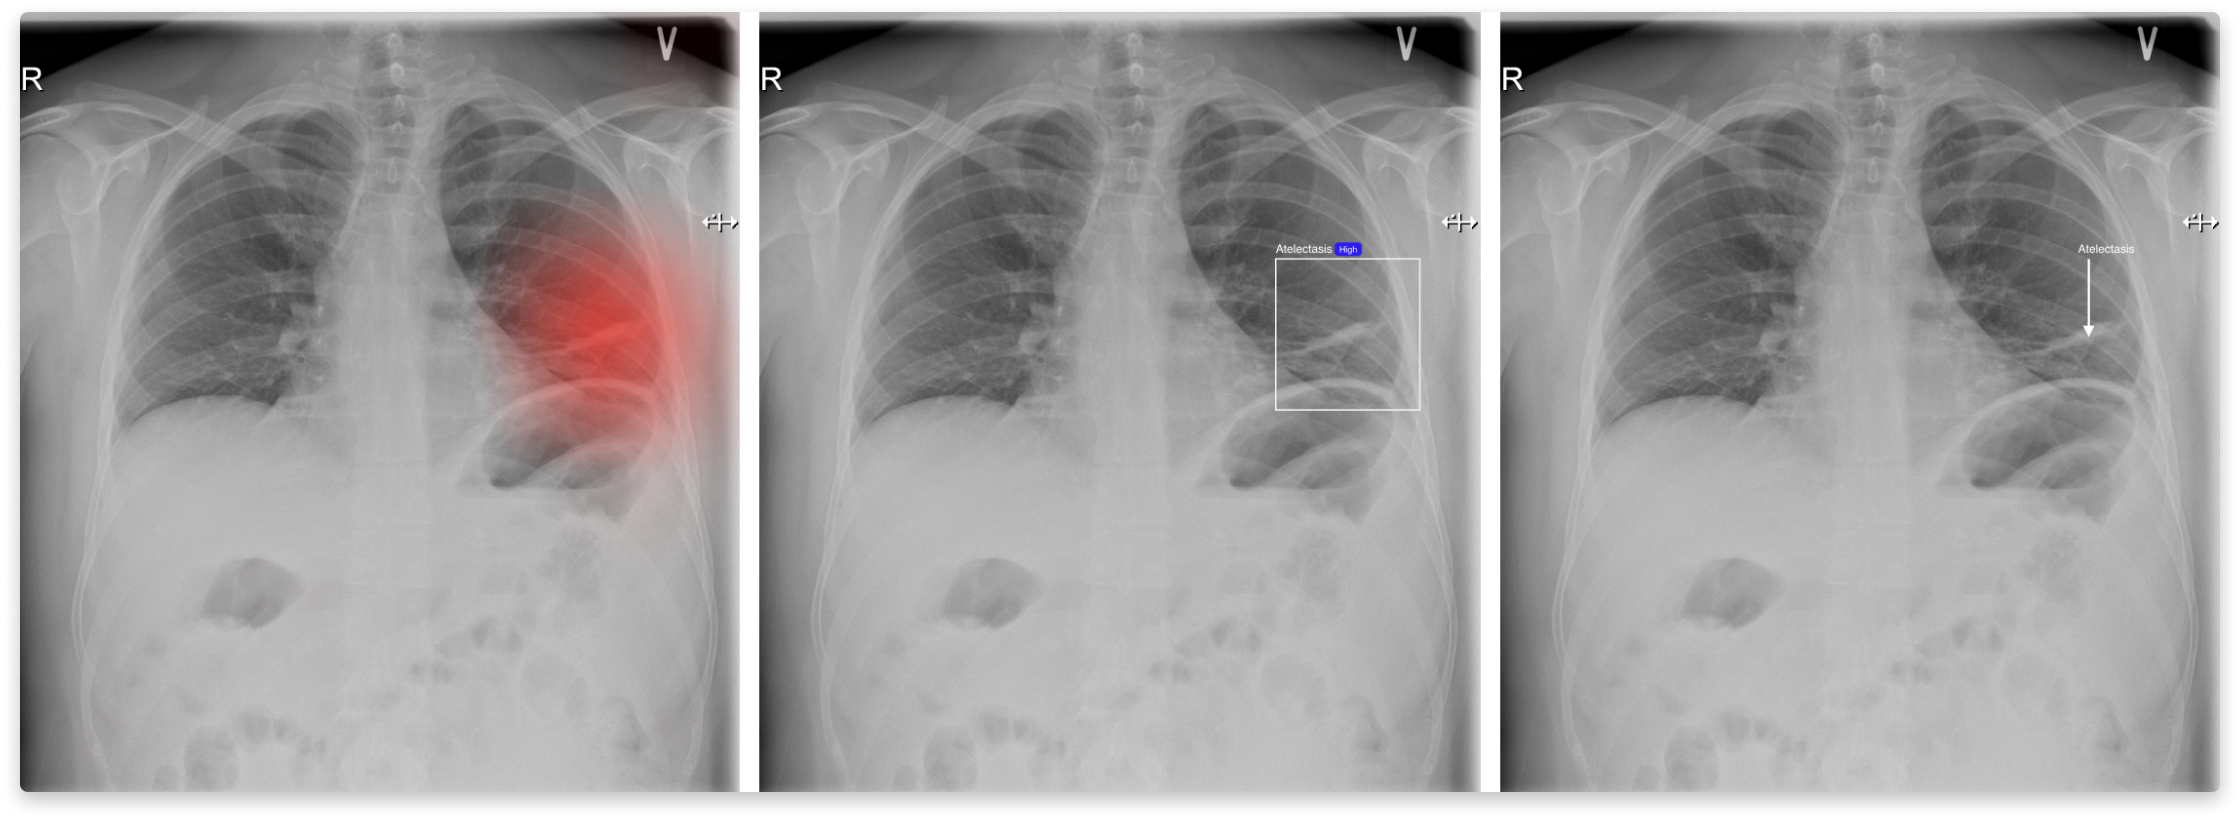

A series of three X-ray images showing the human chest, with annotations highlighting specific areas of interest in the lungs. The first image has a red highlighted area on one of the lungs, the second image has a blue rectangular box around the same area, and the third image has an arrow pointing to that area.

How should the AI explain its decisions? Understanding AI predictions supports building trust towards AI-based systems. In this study, we explored three visual ways of explaining AI predictions: heat maps, bounding boxes, and arrows (see Fig. 8). We discovered that no single method can support the explainability of all the radiological findings.

The visual appearance of radiological findings dictates the best way to highlight them for radiologists for inspection. Radiologists discern between different radiological findings based on their visual appearance. Their presentation ranges from barely visible nodules to diffused opacities (areas of less transparency) present across both lungs. The breadth of visual impressions suggests the need for flexibility, I think that both ways of displaying the findings are fine, but for different pathologies. I mean, the heat map makes sense in this case for pneumothorax because it’s a very extensive finding. And for the fracture, it makes sense to see it with a box, whereas the heat map doesn’t make that much sense. It becomes too blurry… [S13, Senior, Specialised hospital, Denmark]. Radiologists preferred bounding boxes for more contained findings, whereas the more diffused, the more inclined they were towards the heat map. An important factor when designing XAI for chest X-rays is allowing for inspection of the underlying examination. The main purpose of XAI is to direct radiologists’ attention to the detected findings. To assess the validity of a prediction, radiologists have to inspect the examination itself without additional overlays.